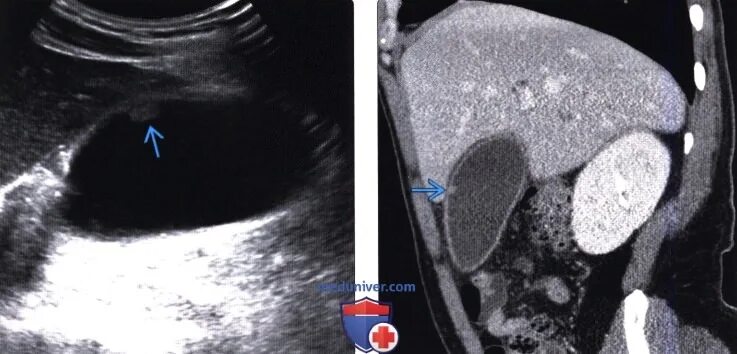

Удалить полипы в желчном